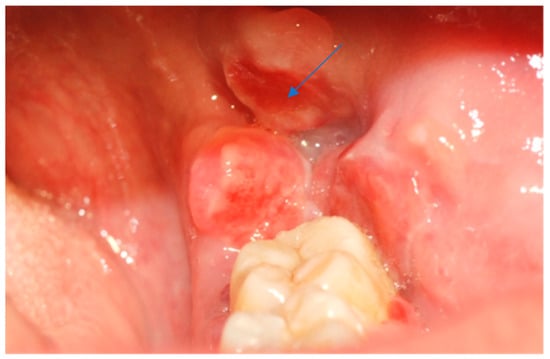

A 39-year-old Caucasian woman was referred by her dentist to the Department of Oral Sciences and Maxillofacial Surgery, Polyclinic Umberto I, “Sapienza” University of Rome, for evaluation of multiple exophytic and erythematous lesions in the left retromolar region (Figure 1). The lesions had been present for approximately five months and were associated with occasional minor bleeding following local trauma. The patient also reported mild pain and a recent increase in the size of the lesions during the two weeks preceding the visit. Her medical history included systemic lupus erythematosus (SLE), diagnosed in 2000 at the Department of Clinical Medicine, “Sapienza” University of Rome, following symptoms of gastroesophageal reflux, low-grade fever, diffuse arthromyalgia, a previous pericardial effusion, and positivity for ANA and ENA SS-A antibodies. She was under treatment with prednisone and cyclophosphamide, levothyroxine sodium for hypothyroidism, and omeprazole for gastroesophageal reflux. The patient was allergic to penicillins and denied regular tobacco or alcohol use. In 2015, she developed ocular vasculitis with photosensitivity, prompting replacement of cyclosporine with cyclophosphamide.

Figure 1.

Erythematous and exophytic lesion located on the left retromolar trigone. The blue arrow indicates the lesion located at the retromolar trigone.